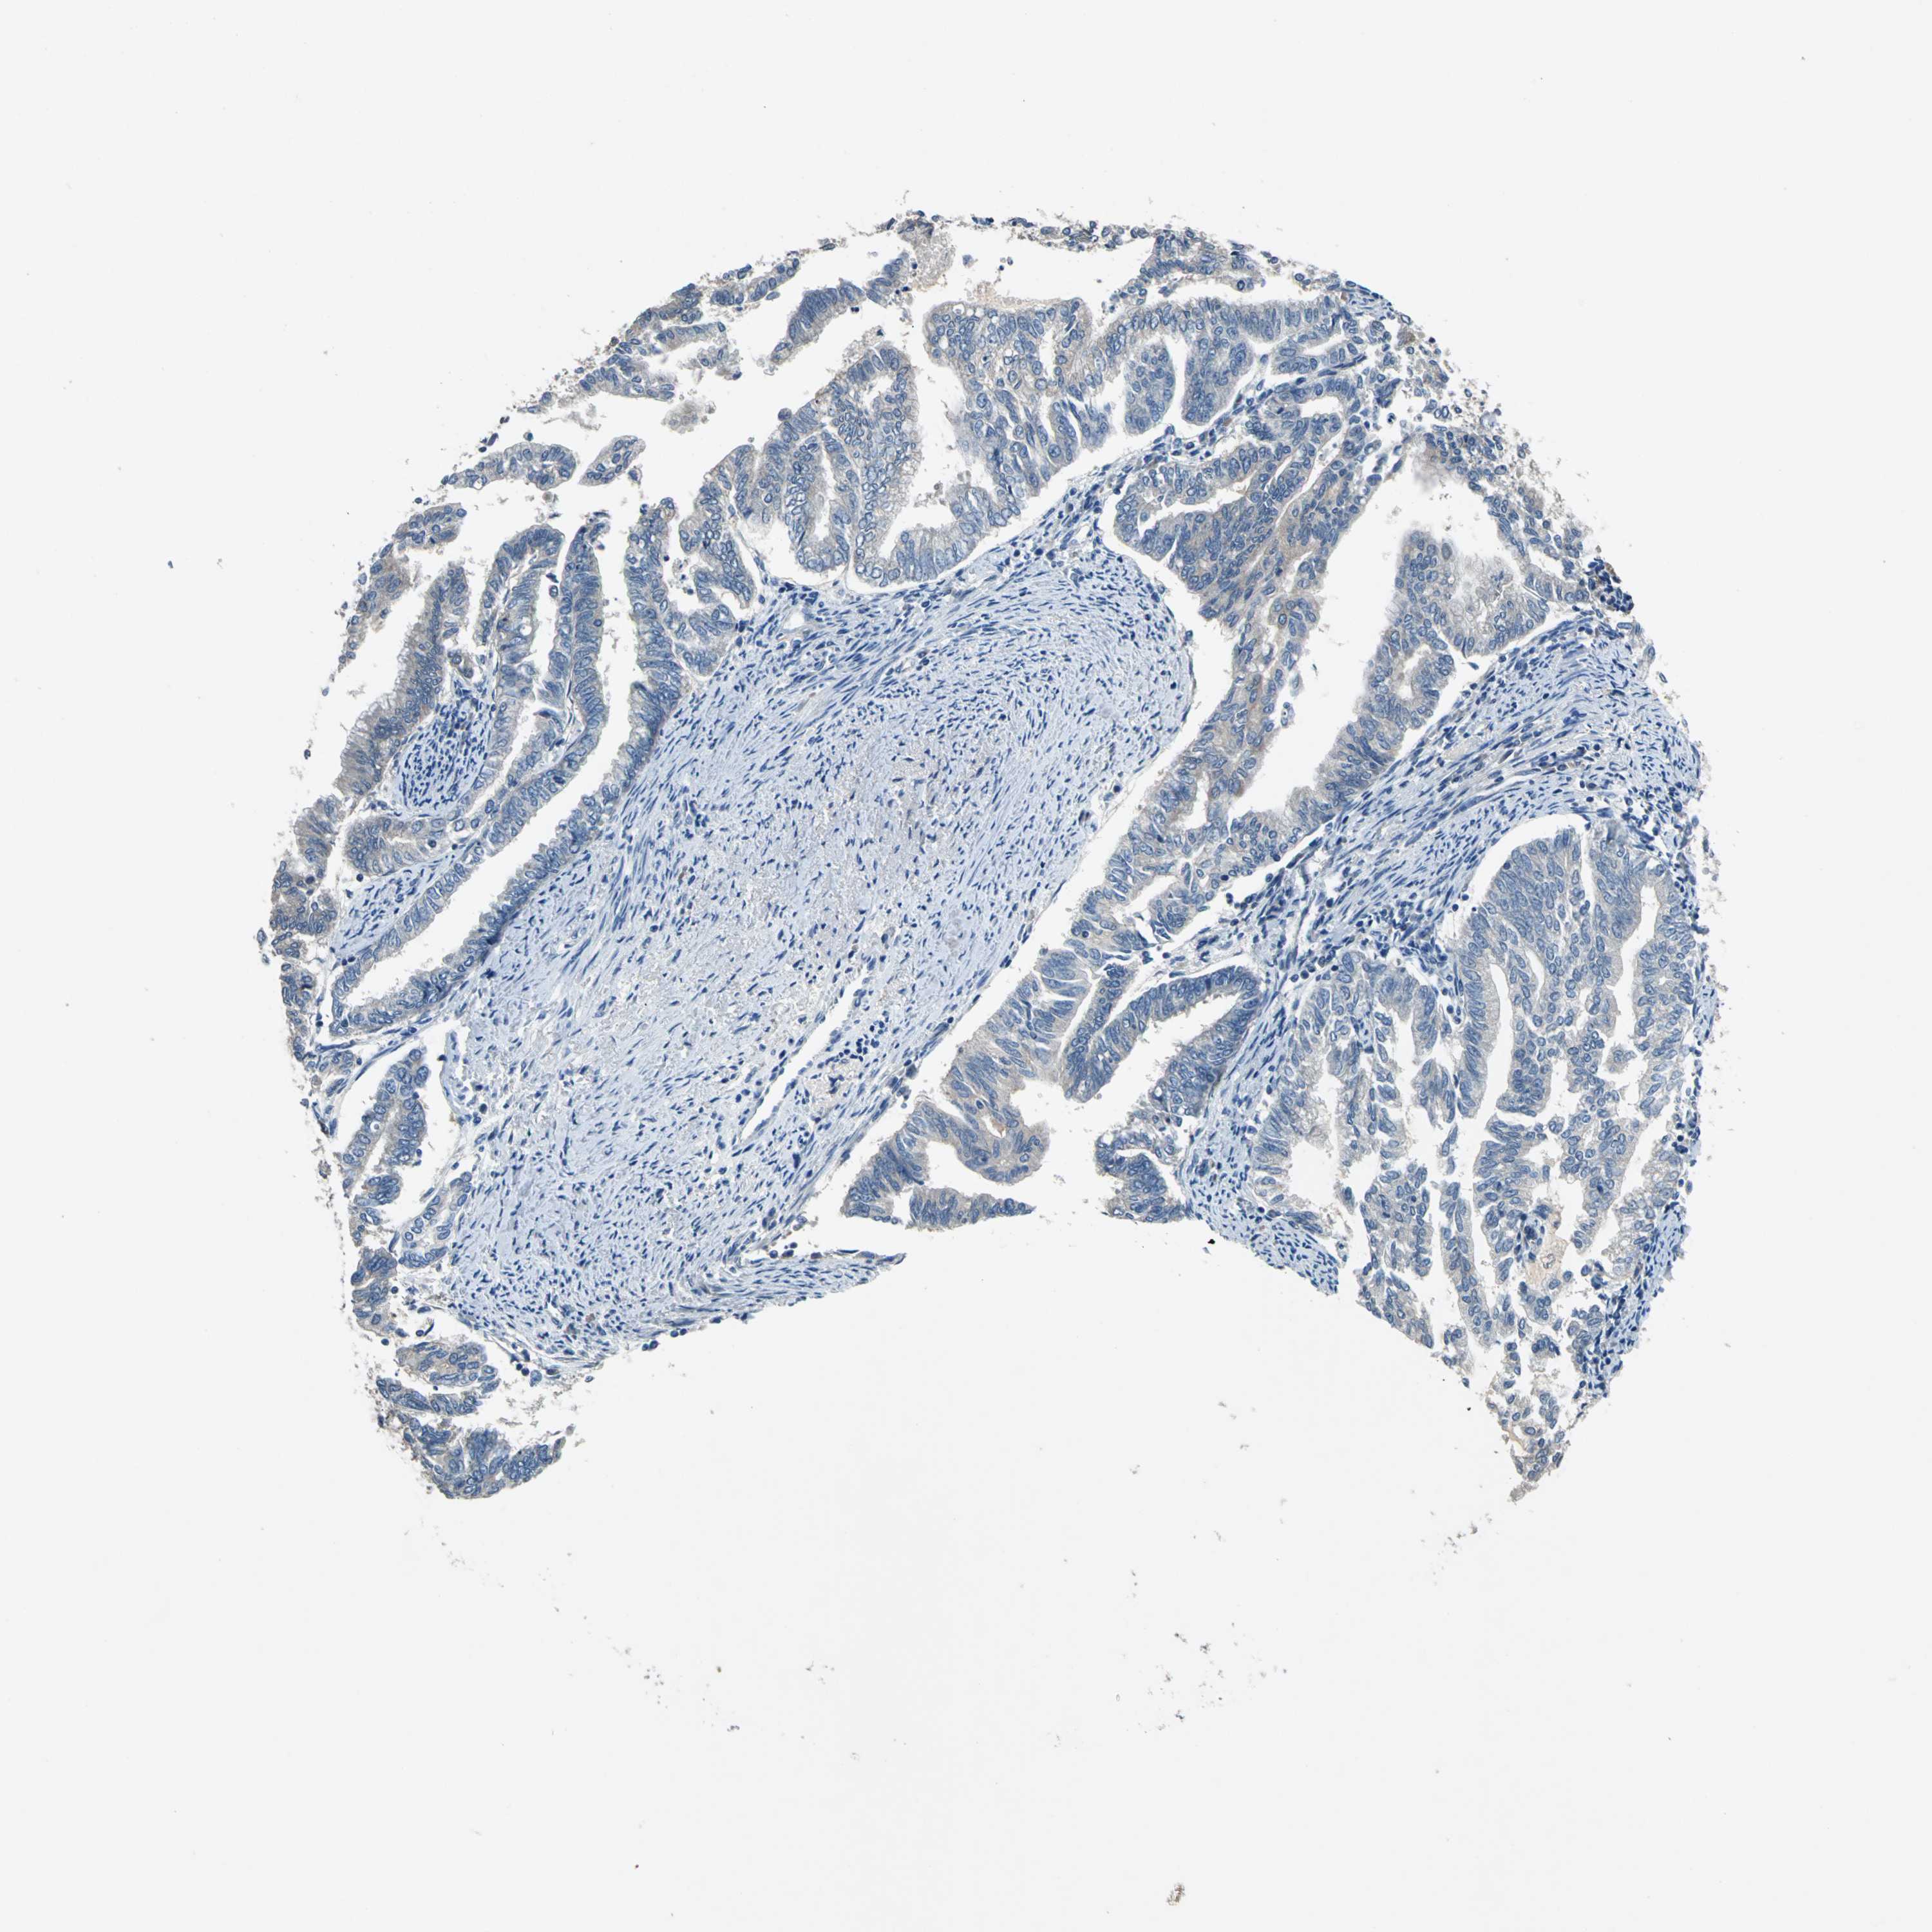

ENDOMETRIAL CANCER - Protein expressioni

A mouse-over function shows sample information and annotation data. Click on an image to view it in a full screen mode. Samples can be filtered based on level of antibody staining by selecting one or several of the following categories: high, medium, low and not detected. The assay and annotation is described here.

Note that samples used for immunohistochemistry by the Human Protein Atlas do not correspond to samples in the TCGA dataset.

Antibody stainingi

Antibody staining in the annotated cell types in the current human tissue is reported as not detected, low, medium, or high, based on conventional immunohistochemistry profiling in selected tissues. This score is based on the combination of the staining intensity and fraction of stained cells.

Each image is clickable and will lead to virtual microscopy that enables deeper exploration of all samples and also displays staining intensity scores, fraction scores and subcellular localization as well as patient and tissue information for each sample.

Antibody HPA006563

Antibody HPA006564

Antibody CAB003844

Antibody CAB016290